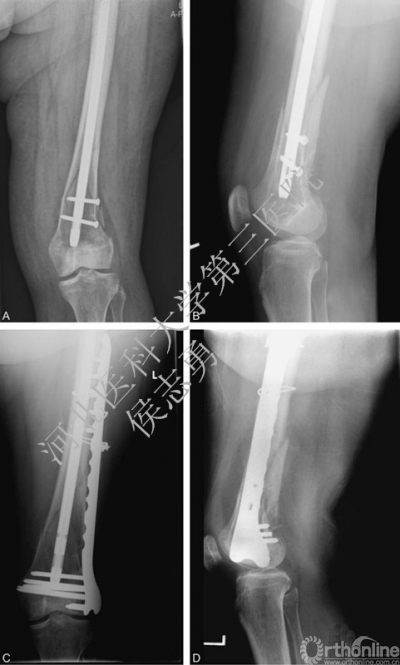

图3 A和B为初次手术采用长髓内钉固定术后6个月,患者再次外伤,长髓内远端处骨折。C和D,远端锁定钢板固定术后的正侧位片,治疗后6个月,愈合虽然缓慢但仍在进展,摄片时患者康复良好,完全无痛。